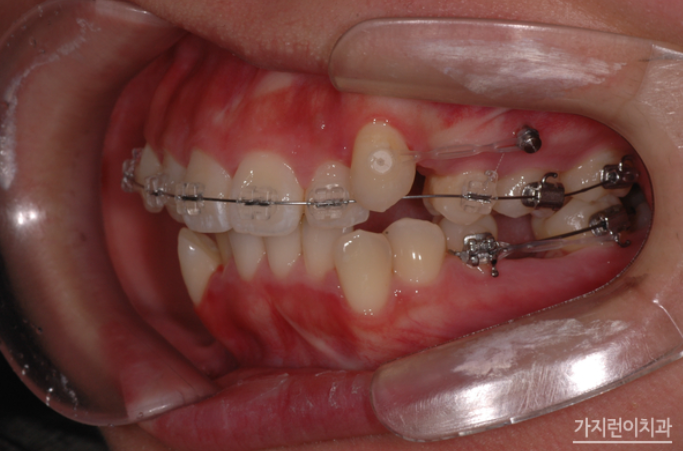

위 환자의 경우 상악 돌출입 증상과 더불어 심한 충치로 인해 발치가 불가피한 악조건을 갖고 있었는데요. 충치는 정도가 심하면 결국 발치를 하게 되고 인공치아를 식립해야 하는 과정을 밟게 되는데요. 그런데 환자의 경우 불규칙적인 치열의 재배열과 더불어 콤플렉스로 자리잡은 돌출입도 교정으로 진행해볼 수 있었습니다. Modified Bonded Cantilever Spring (MBC spring) 교정으로 사랑니에 직접 부착해 사랑니를 세우는 교정을 진행하게 되었는데요. 사랑니가 쓰러져 있는 상태라면 기존의 교정장치를 부착하기 어렵기 때문에 개발된 장치를 사용하고 있습니다. 그러면 장치를 착용한 후의 경과를 볼까요?

하지만 사랑니를 세우는 교정이라고 해서 모든 사람이 Modified Bonded Cantilever Spring (MBC spring) 교정을 사용하지는 않는데요. 환자분의 경우 하악 어금니 발치 공간을 메우는 과정에서 사랑니가 쓰러져 있긴 했지만 교정장치를 부착할 수 있는 상황이었기 때문에 추가적으로 Modified Bonded Cantilever Spring (MBC spring)을 사용하지는 않았습니다. 대신 돌출입 해결을 위해 상악을 후방으로 이동하기 위해 교정용 스크류를 이용해 진행하게 되었는데요. 총 2년 3개월의 치료기간이 소요된 환자분의 교정전후 사진을 확인해볼까요?